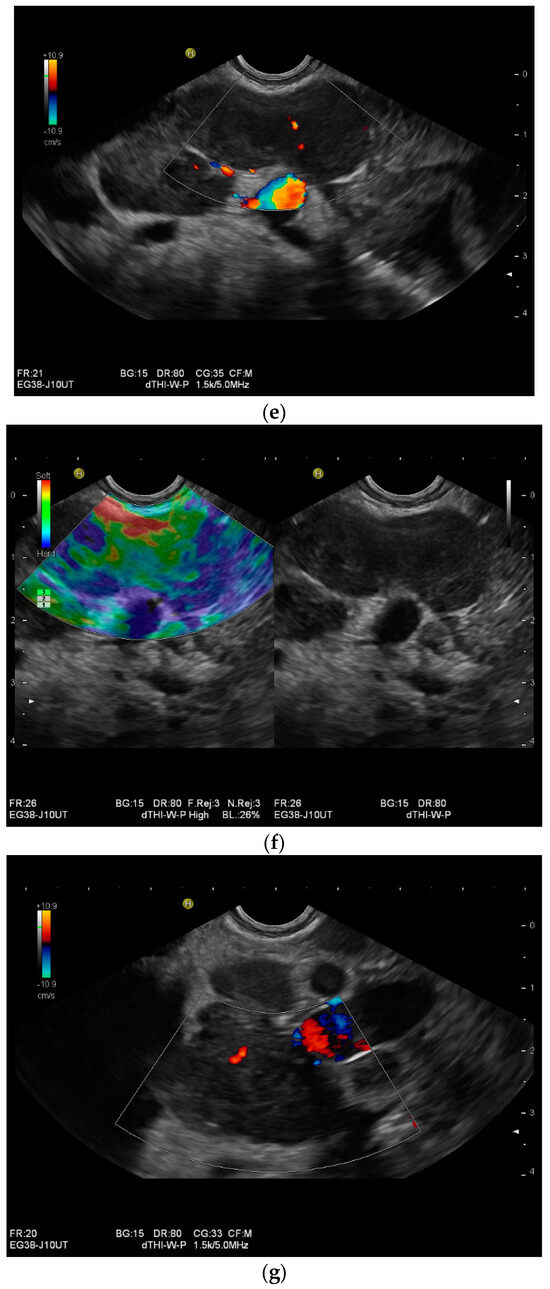

Figure 1.

Typical changes in the peritoneum, mesentery, and omentum in patients with tuberculosis. Ascites with pronounced septa (a). Ascites encapsulated between the abdominal wall and colon (b). Omental thickening with non-echoic caseous abscesses and few echogenic contents (c); hypoechoic nodules in hyperechoic thickened peritoneum (d). Significantly thickened hyperechoic peritoneum in B-mode US (right side of image) (marked with arrows). In CEUS, the thickened peritoneum is contrast enhanced in the arterial phase (e). In the parenchymal phase, it shows a decrease in enhancement (f). The thickened hyperechoic peritoneum shows a non-echoic lesion (arrow) (g). In the CEUS, this is not enhanced and instead shows a hyperenhanced rim. This corresponds to caseous necrosis (h).